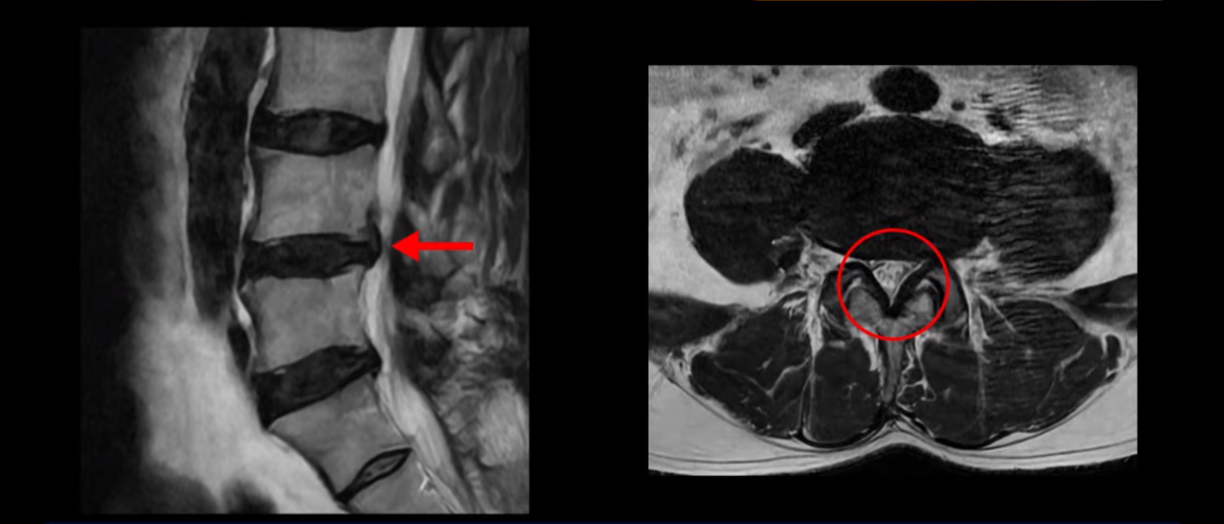

하지만 이분의 갑작스러운 통증을 일으키는 원인은 4번 5번에 발생한 디스크 파열입니다.

이분은 왼쪽 무릎 아래로 본인 표현으로는 다리를 잘라 버리고 싶다고 할 정도의 심한 통증이 있는데 보통 이런 표현은 디스크 파열이 발생했을 때 많이 사용하는 표현입니다. 이분 4번 5번 디스크를 자세히 보면 왼쪽으로 파열되어 밀려 올라간 디스크 수핵을 볼 수 있습니다.

옆에서도 보이지만 단면에서도 왼쪽으로 심하게 밀려나온 수핵이 잘 보입니다.